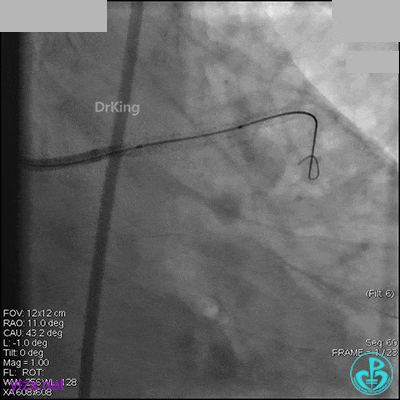

右冠脉中段充分扩张后欲植入3.5×38mm支架时,支架难以通过中远段扭曲处,且指引导管、导丝弹出飞扬。反复尝试导丝重新到达右冠脉远端时通过不顺利,局部造影剂滞留,远端血流接近3级。

右冠脉血流3级,患者无症状,终止手术。

术后患者无特殊不适。